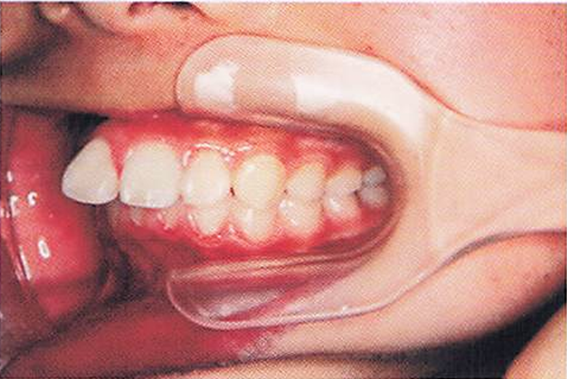

午前-55

10歳の女児。上顎前歯の歯ならびが気になることを主訴として来院した。 顔面写真、口腔内写真および治療に用いた装置の写真を別に示す。 期待できる効果はどれか。1つ選べ。

a.下顎前歯の唇側移動

b.下顎骨の前方成長促進

c.上顎大臼歯の近心移動

d.上顎骨の前方成長抑制

解答を見る

d